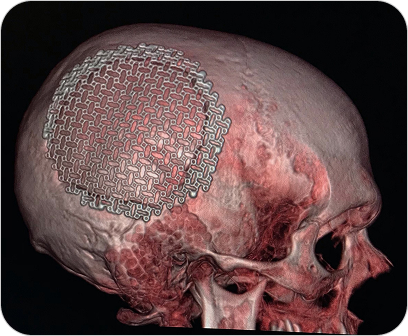

Reconstrucción 3D en Tomografía

Es una técnica avanzada que permite convertir las imágenes obtenidas por tomografía computada en modelos tridimensionales. Estas reconstrucciones permiten visualizar estructuras anatómicas de forma realista, facilitando diagnósticos más precisos y una mejor planificación quirúrgica o terapéutica.

Las reconstrucciones tridimensionales a partir de tomografía computada permiten visualizar la anatomía de forma realista y precisa, facilitando diagnósticos y cirugías complejas.

¿PARA QUE SE UTILIZA?

- Evaluación detallada de fracturas complejas, articulaciones y columna vertebral.

- Estudio anatómico previo a cirugías (traumatológicas, maxilofaciales, cardiovasculares).

- Visualización de vasos sanguíneos, tumores o malformaciones desde distintos ángulos.

- Planificación prequirúrgica más segura y personalizada.

- Educación médica y explicación visual a pacientes.

¿POR QUÉ ES UN ESTUDIO DESTACADO?

- Imágenes más claras y comprensibles para médicos y pacientes.

Facilita una mayor precisión diagnóstica. - Permite una visión global y tridimensional de la anatomía.

- Complemento ideal para especialidades como traumatología, neurocirugía, cirugía maxilofacial y oncología.

Reconstrucción 3D en Tomografía

Es una técnica avanzada que permite convertir las imágenes obtenidas por tomografía computada en modelos tridimensionales. Estas reconstrucciones permiten visualizar estructuras anatómicas de forma realista, facilitando diagnósticos más precisos y una mejor planificación quirúrgica o terapéutica.

Las reconstrucciones tridimensionales a partir de tomografía computada permiten visualizar la anatomía de forma realista y precisa, facilitando diagnósticos y cirugías complejas.

¿PARA QUE SE UTILIZA?

- Evaluación detallada de fracturas complejas, articulaciones y columna vertebral.

- Estudio anatómico previo a cirugías (traumatológicas, maxilofaciales, cardiovasculares).

- Visualización de vasos sanguíneos, tumores o malformaciones desde distintos ángulos.

- Planificación prequirúrgica más segura y personalizada.

- Educación médica y explicación visual a pacientes.

¿POR QUÉ ES UN ESTUDIO DESTACADO?

- Imágenes más claras y comprensibles para médicos y pacientes.

Facilita una mayor precisión diagnóstica. - Permite una visión global y tridimensional de la anatomía.

- Complemento ideal para especialidades como traumatología, neurocirugía, cirugía maxilofacial y oncología.